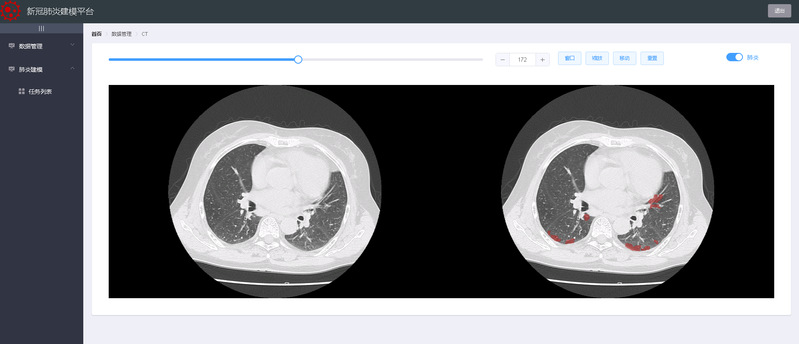

CT图像与肺炎区域对照

近日,由sunbet申慱官网感知计算研究中心王宽全教授团队研发出“新冠肺炎在线建模平台”软件,现已部署到云平台并投入应用。该系统率先将人工智能技术、云计算技术和计算机图形学综合应用于临床胸部CT图像分析,不仅能实现全天候24小时不间断服务,打破传统医学分析软件部署应用过程中时间和空间的限制,同时能够在2分钟之内实现全自动识别肺部新冠肺炎病灶区域,在辅助医生临床诊断新冠肺炎患者病情方面发挥了重要作用。

经过多轮论证和科学对比分析,该系统能够较好地实现多期新冠肺炎患者肺部器官和病灶的快速识别,并实现三维可视化,时间效率较目前主流软件大大提高,有效提升了医生诊断的工作效率,同时可以计算出肺炎体积并进行定量分析,作为诊断的重要参考依据。